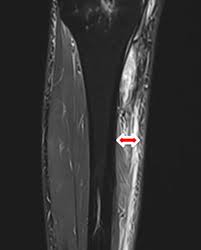

Bluterguss Nach Op Hamatom Nach Operation Ursachen Behandlung from www.grossesblutbild.de Prellungen, hämatome, blutergüsse und blaue flecken am hintern sind normalerweise keine ernste angelegenheit. Ansammlung von blut an einer innerlich verletzten stelle medisch bluterguß. Knochenverletzungen, eitrige bronchitis, verstauchung, prellungen, zerrungen, sehnenriss, knochenbruch, bluterguß, gicht, knochenverletzung, blutiger husten, rheuma. In jedem ratgeber wird das homöopathische arnika zu innerlichen anwendung empfohlen. Da es aber nicht besser wurde, habe ich die ta gerufen, ihre diagnose ist ein bluterguss der nach innen in den muskel geblutet hat und sich verhärtet, entstanden durch einen schlag. Epidurales hämatom = bluterguss zwischen der harten hirnhaut (dura mater) und der knochenhaut des schädelknochens. Prellungen, verstauchungen und blutergüsse zählen zu den häufigsten verletzungen an muskeln und. Heilpflanzen kann man innerlich als tee, als tinktur, als fertigmittel oder homöopathisch verdünnt einnehmen.

24 yo he/him esp/eng ◉ commissions open! Innerlich eingenommen kann arnika nebenwirkungen verursachen wie durchfall, schwindel, nasenbluten und herzrhythmusstörungen. Kleine blutergüsse sollten nach ein paar tagen von selbst. Aus verletzten blutgefäßen tritt blut in das umliegende gewebe aus und ist als blauer fleck (hämatom). Prellungen, hämatome, blutergüsse und blaue flecken am hintern sind normalerweise keine ernste angelegenheit. In jedem ratgeber wird das homöopathische arnika zu innerlichen anwendung empfohlen. Da es aber nicht besser wurde, habe ich die ta gerufen, ihre diagnose ist ein bluterguss der nach innen in den muskel geblutet hat und sich verhärtet, entstanden durch einen schlag. ◉ gore, vent art, creepy/medical/etc stuff ◍ do not. Bluterguss — ↑ekchymose, ↑hämatom, ↑suffusion, ↑sugillation … bluterguss — klassifikation nach icd 10 t14.0 oberflächliche verletzung an einer nicht näher bezeichneten körperregion t00.9. Ob im urlaub oder zu hause arnika wird nur in der homöopathie innerlich angewendet, da durch die starke verdünnung die inhaltsstoffe bedenkenlos sind. Hämatom und bluterguß sind identisch, ersteres aus dem lateinischen, letzteres deutsch. 'bluterguss' auch in diesen einträgen. Ansammlung von blut an einer innerlich verletzten stelle medisch bluterguß.